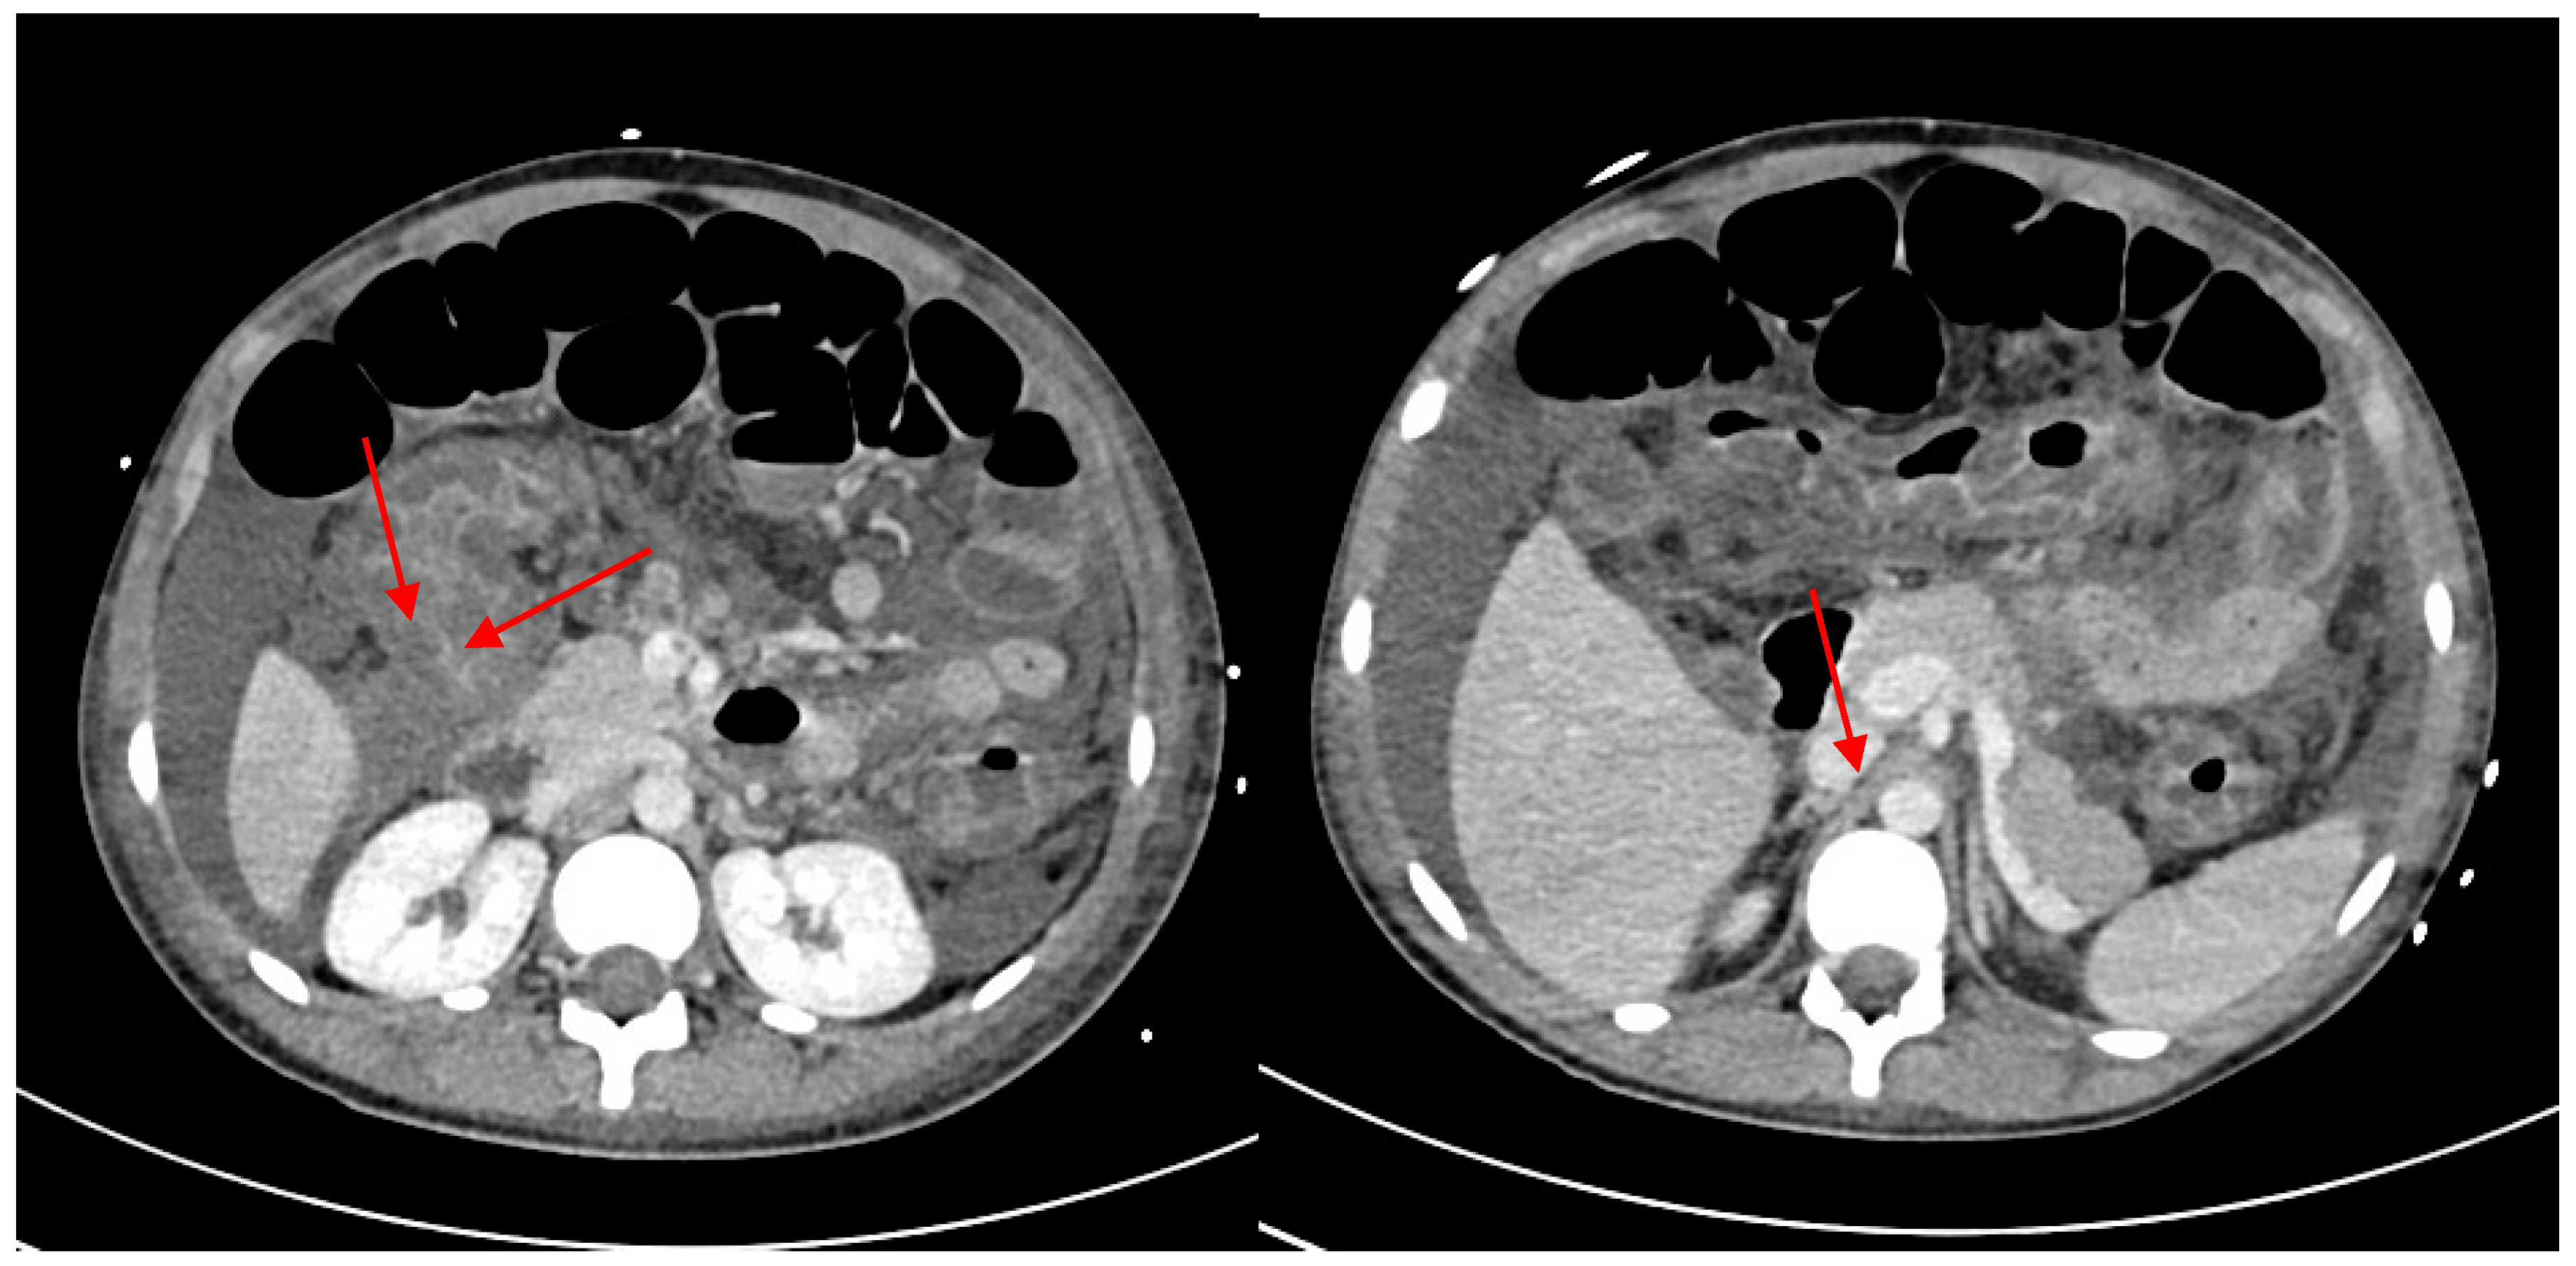

Severe Typhoid Fever Complicated by Superior Mesenteric and Splenic Vein Thrombosis

2. Case Description